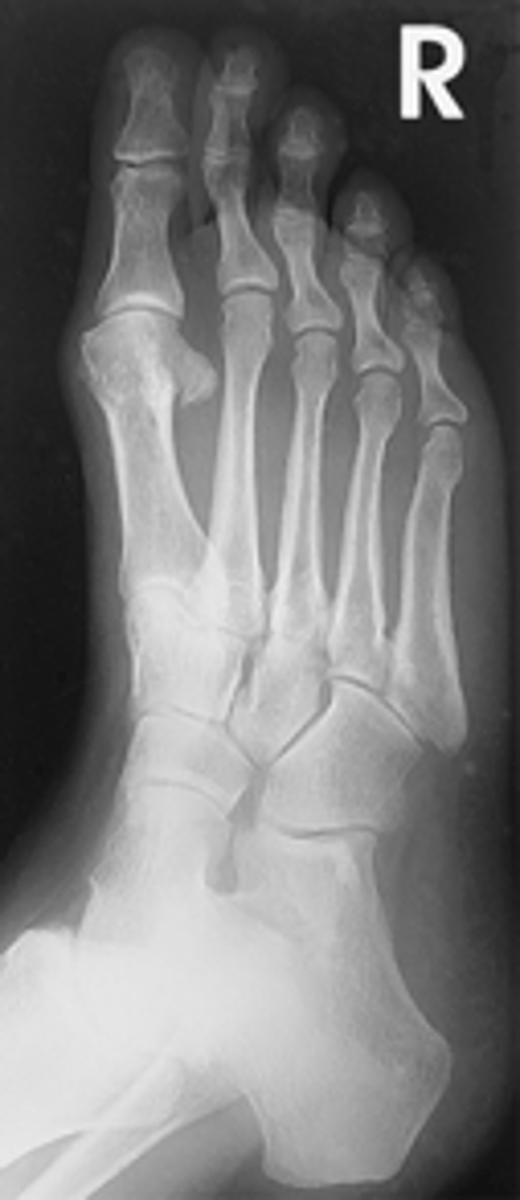

AP Oblique Foot

What projection is this?

Evaluation Criteria for AP Oblique Foot

- 30° to 40° medial rotation

- CR to base of third MT

- Entire foot visualized

- Third through fifth metatarsals free of superimposition

- Tuberosity demonstrated at base of fifth metatarsal

- Optimal exposure factors